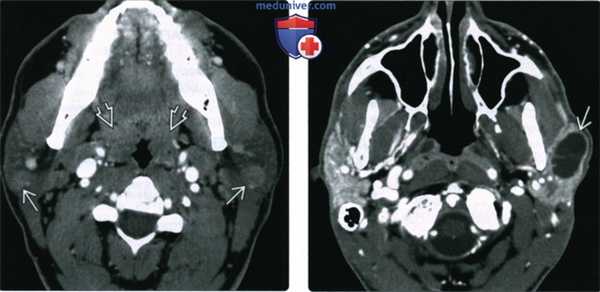

(Слева) КТ с КУ, аксиальная проекция. В обеих околоушных железах визуализируются солидные образования с четкими контурами. И хотя метастазы и лимфома могут выглядеть точно так же, гипертрофия небных миндалин позволяет заподозрить лимфоэпителиальное поражение или хроническую лимфаденопатию околоушных лимфоузлов при ВИЧ.

(Справа) КТ с КУ, единичная киста в левой околоушной железе, разделенная внутренней перегородкой. И хотя при доброкачественном лимфоэпителиальном поражении обычно обнаруживается сразу несколько образований, иногда они могут быть и единичными. В такой ситуации может быть выставлен неверный диагноз - киста первой жаберной щели.

(Слева) На аксиальной КТ с КУ визуализируются хорошо отграниченные солидные контрастиру-ющиеся очаги в обеих околоушных железах. Метастазы и лимфома могут выглядеть аналогично, но гипертрофия миндалин позволяет предположить ДЛЭП или персистирующую лимфаде-нопатию околоушных желез, обусловленную ВИЧ.

(Справа) На аксиальной КТ с КУ в левой околоушной железе визуализируется солитарное образование, разделенное перегородками. ДЛЭП обычно являются множественными, но возможны и солитарные поражения.